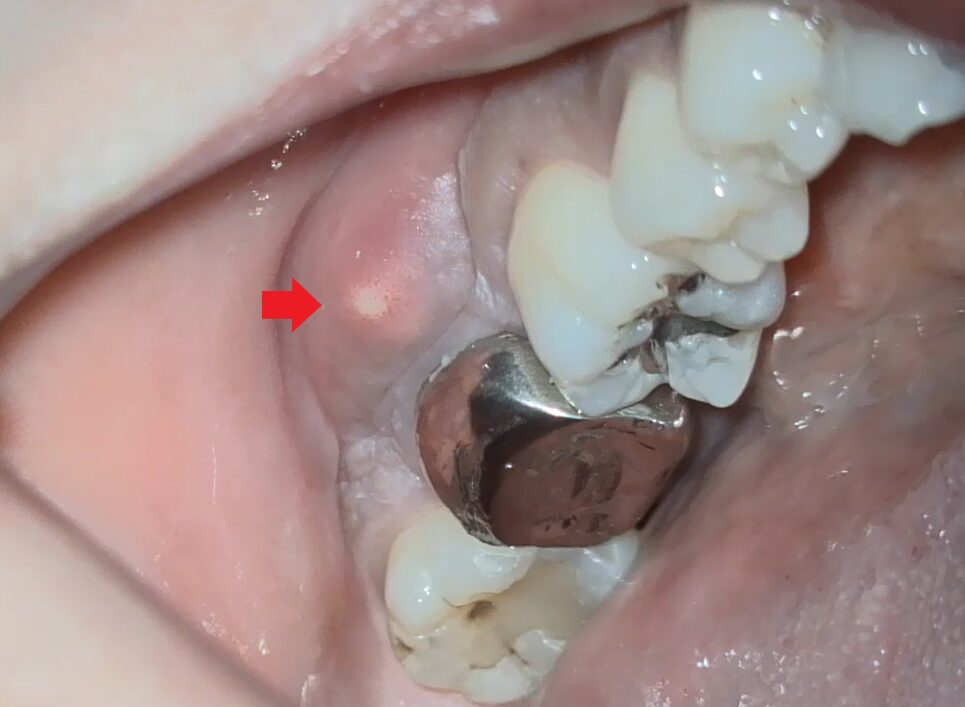

Photo.フィステル

赤い矢印の先に白い膿が見られます。